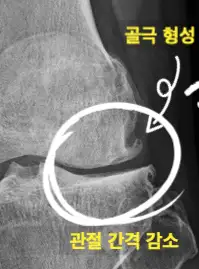

✅ 무릎관절염은 환자의 증상 및 신체검사 그리고 방사선 촬영검사 결과를 바탕으로 진단하게 되는데요. X-ray 검사로 관절 간격이 얼마나 좁아졌는지 그리고 관절 주변의 골 변형이 얼마나 심한지 등을 기준으로 초기, 중기, 말기 단계로 구분합니다.

⭐ 골극이란? ⭐

💡 골증식체라고 부르며 뼈에서 자라는 부드러운 뼈덩어리입니다.

보통 두 개 이상의 뼈가 만나는 관절 근처에서 오랜 시간에 걸쳐 만들어지며 주변 신경을 자극해 염증을 유발하거나 관절운동 범위를 제한하기도 합니다.

👉무릎 관절 통증과 관절 주변이 붓는걸 더 자주 느끼기 시작합니다. 엑스레이 검사에서도 관절 간격이 초기보다 좁아지고 골극 형성 등이 확인됩니다.